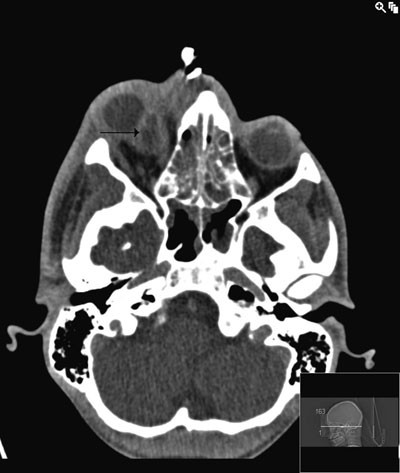

To dager etter andre operasjon hadde pasienten økende retrobulbære smerter over høyre øye. Ny CT-undersøkelse med kontrast viste økning av abscess bak bulbus occuli, mellom nervus opticus og musculus rectus medialis (fig 3).

Abscessen var vanskelig å nå gjennom øre-nese-hals-tilgang og vi tok derfor kontakt med Øyeavdelingen for samarbeid.